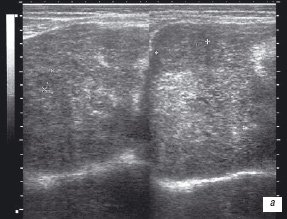

Больной Х. направлен кардиологом для проведения УЗИ сердца (по поводу ишемической болезни сердца, стабильной стенокардии напряжения III ФК: НIIА) и гепатобилиарной зоны (в связи с жалобами на ноющие боли, чувство тяжести в правом подреберье). При проведении эхографии печени размеры последней соответствовали верхней границе нормы. Паренхима визуализировалась диффузно неоднородной, в ней лоцировались гипо- и изоэхогенные округлые и овальные образования различного размера (от 1,5 до 4,8 см) преимущественно с неоднородной внутренней структурой, несколько нечеткими контурами (рис. 1 а,б).

а) Косое сканирование.